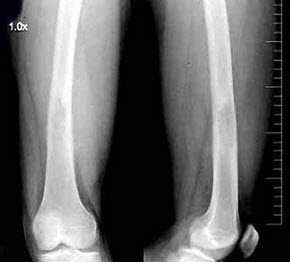

女,48岁,车祸致右胫腓骨骨折,外固定术后两年复查,如图所示,最可能的诊断是()

A.右胫骨愈合延迟

B.右胫骨假关节形成

C.右胫骨骨折愈合好,有大量骨痂形成

D.右胫骨断端不连

E.以上均不正确